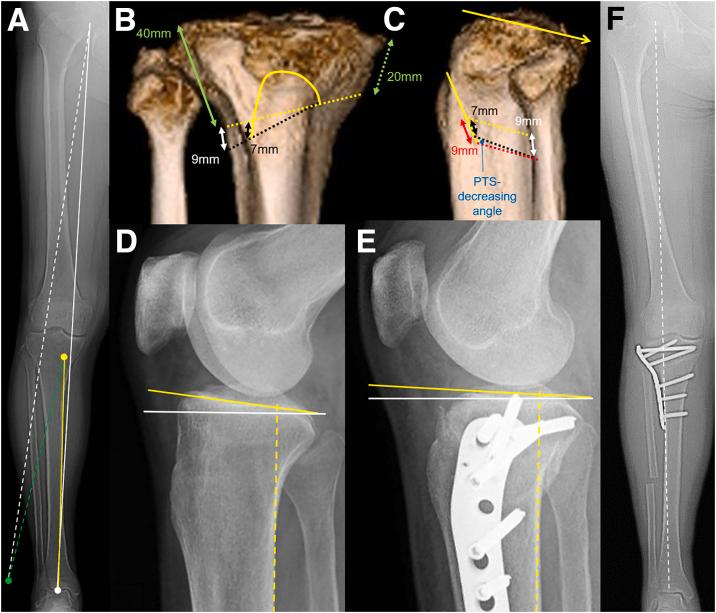

In conventional closed-wedge high tibial osteotomy (CWHTO) with preservation of the medial hinge, flexion contracture cannot be improved because of the two-dimensional correction. Conversely, in hybrid CWHTO, for which the name is derived from a hybrid of the lateral closing and medial opening, the medial cortex is intentionally disrupted. The medial hinge disruption enables three-dimensional correction, which helps eliminate flexion contracture by decreasing posterior tibial slope (PTS). The fine adjustment of the anterior closing distance and thigh-compression technique further facilitates PTS control. In this study, we describe the use of the Reduction-Insertion-Compression Handle (RICH), which maximizes the benefits of hybrid CWHTO. This device permits accurate osteotomy reduction, easy screw insertion, and assists with providing sufficient compressive force at the osteotomy site, as well as the elimination of the flexion contracture. This Technical Note presents the details of using the RICH and the associated advantages and disadvantages in hybrid CWHTO for medial compartmental knee arthritis.

在保留内侧铰链的传统闭合楔形高位胫骨截骨术(CWHTO)中,由于二维矫正,屈曲挛缩无法改善。相反,在混合式CWHTO中(其名称源于外侧闭合和内侧开口的结合),内侧皮质会被有意破坏。内侧铰链破坏可实现三维矫正,通过减小胫骨后倾坡度(PTS)有助于消除屈曲挛缩。前侧闭合距离的精细调整和大腿加压技术进一步便于控制PTS。在本研究中,我们描述了复位-插入-加压手柄(RICH)的使用,其可最大化混合式CWHTO的益处。该装置可实现精确的截骨复位、轻松的螺钉插入,并有助于在截骨部位提供足够的压缩力,以及消除屈曲挛缩。本技术说明介绍了在混合式CWHTO治疗膝关节内侧间室关节炎中使用RICH的详细情况以及相关的优缺点。